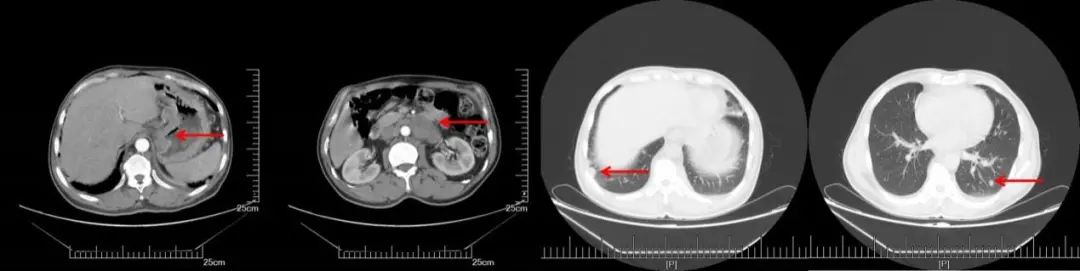

A:CT增强(2016.08.22): 胃体小弯侧增厚,肝胃间、腹膜后多发淋巴结转移,双肺多发转移。B:2周期化疗后CT增强(2016.10.19):胃壁增厚减轻,淋巴结明显缩小,双肺多发转移灶几乎消失

A:CT增强(2017.09.29):右锁骨上,纵膈,腹腔淋巴结明显增大,双肺无明显变化;B:CT增强(2018.03.27):腹膜后多发增大淋巴结较前缩小,右侧锁骨上纵隔内见多发淋巴结,部分较前增大,双肺较前变化不大。